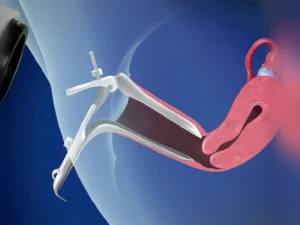

لاپاراسکوپی

لاپاراسکوپی روشی است که پزشک از آن برای بررسی داخل شکم (شکم) و لگن استفاده میکند. این کار با یک لاپاراسکوپ ...

از دلایل لاپاراسکوپی در زنان تشخیص علل نازایی است همچنین زمانی که نیاز است که لوله های رحمی بسته شود، کیست ها تخمدان و فیبروم های رحمی را در آورد میتوان از لاپاراسکوپی استفاده کرد.

خونریزی بعد از لاپاراسکوپی رحم؛ آیا طبیعی است؟ + علائم خطرناک

خونریزی بعد از لاپاراسکوپی رحم در بسیاری از موارد خفیف و موقتی است و میتواند بهدلیل دستکاری رحم، دهانه رحم